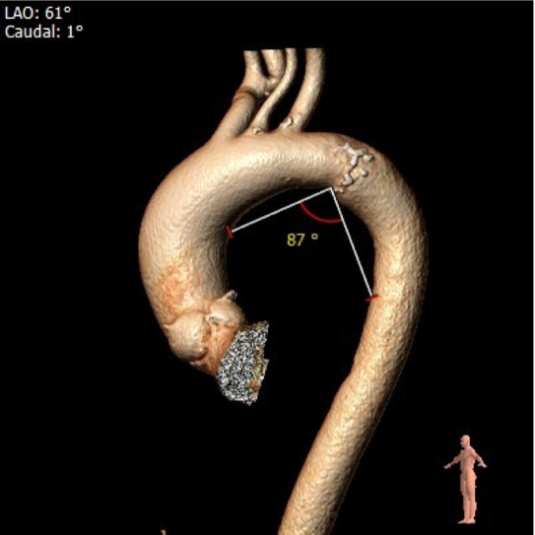

瓦氏窦内径较大,窦管交界内径可,升主动脉扩张

外周血管及主动脉弓解剖

②选择23球囊预扩张,本中心习惯球扩与跨瓣选取右窦中心位,术前CT评估为LAO 4° CRA0° 左右,预装AV29瓣膜;右窦中心位释放人工瓣膜,植入深度推荐标准位(瓣环下2—4mm)。释放后可酌情选择左右重合位(RAO12,CAU24左右)进一步确定人工瓣膜形态。